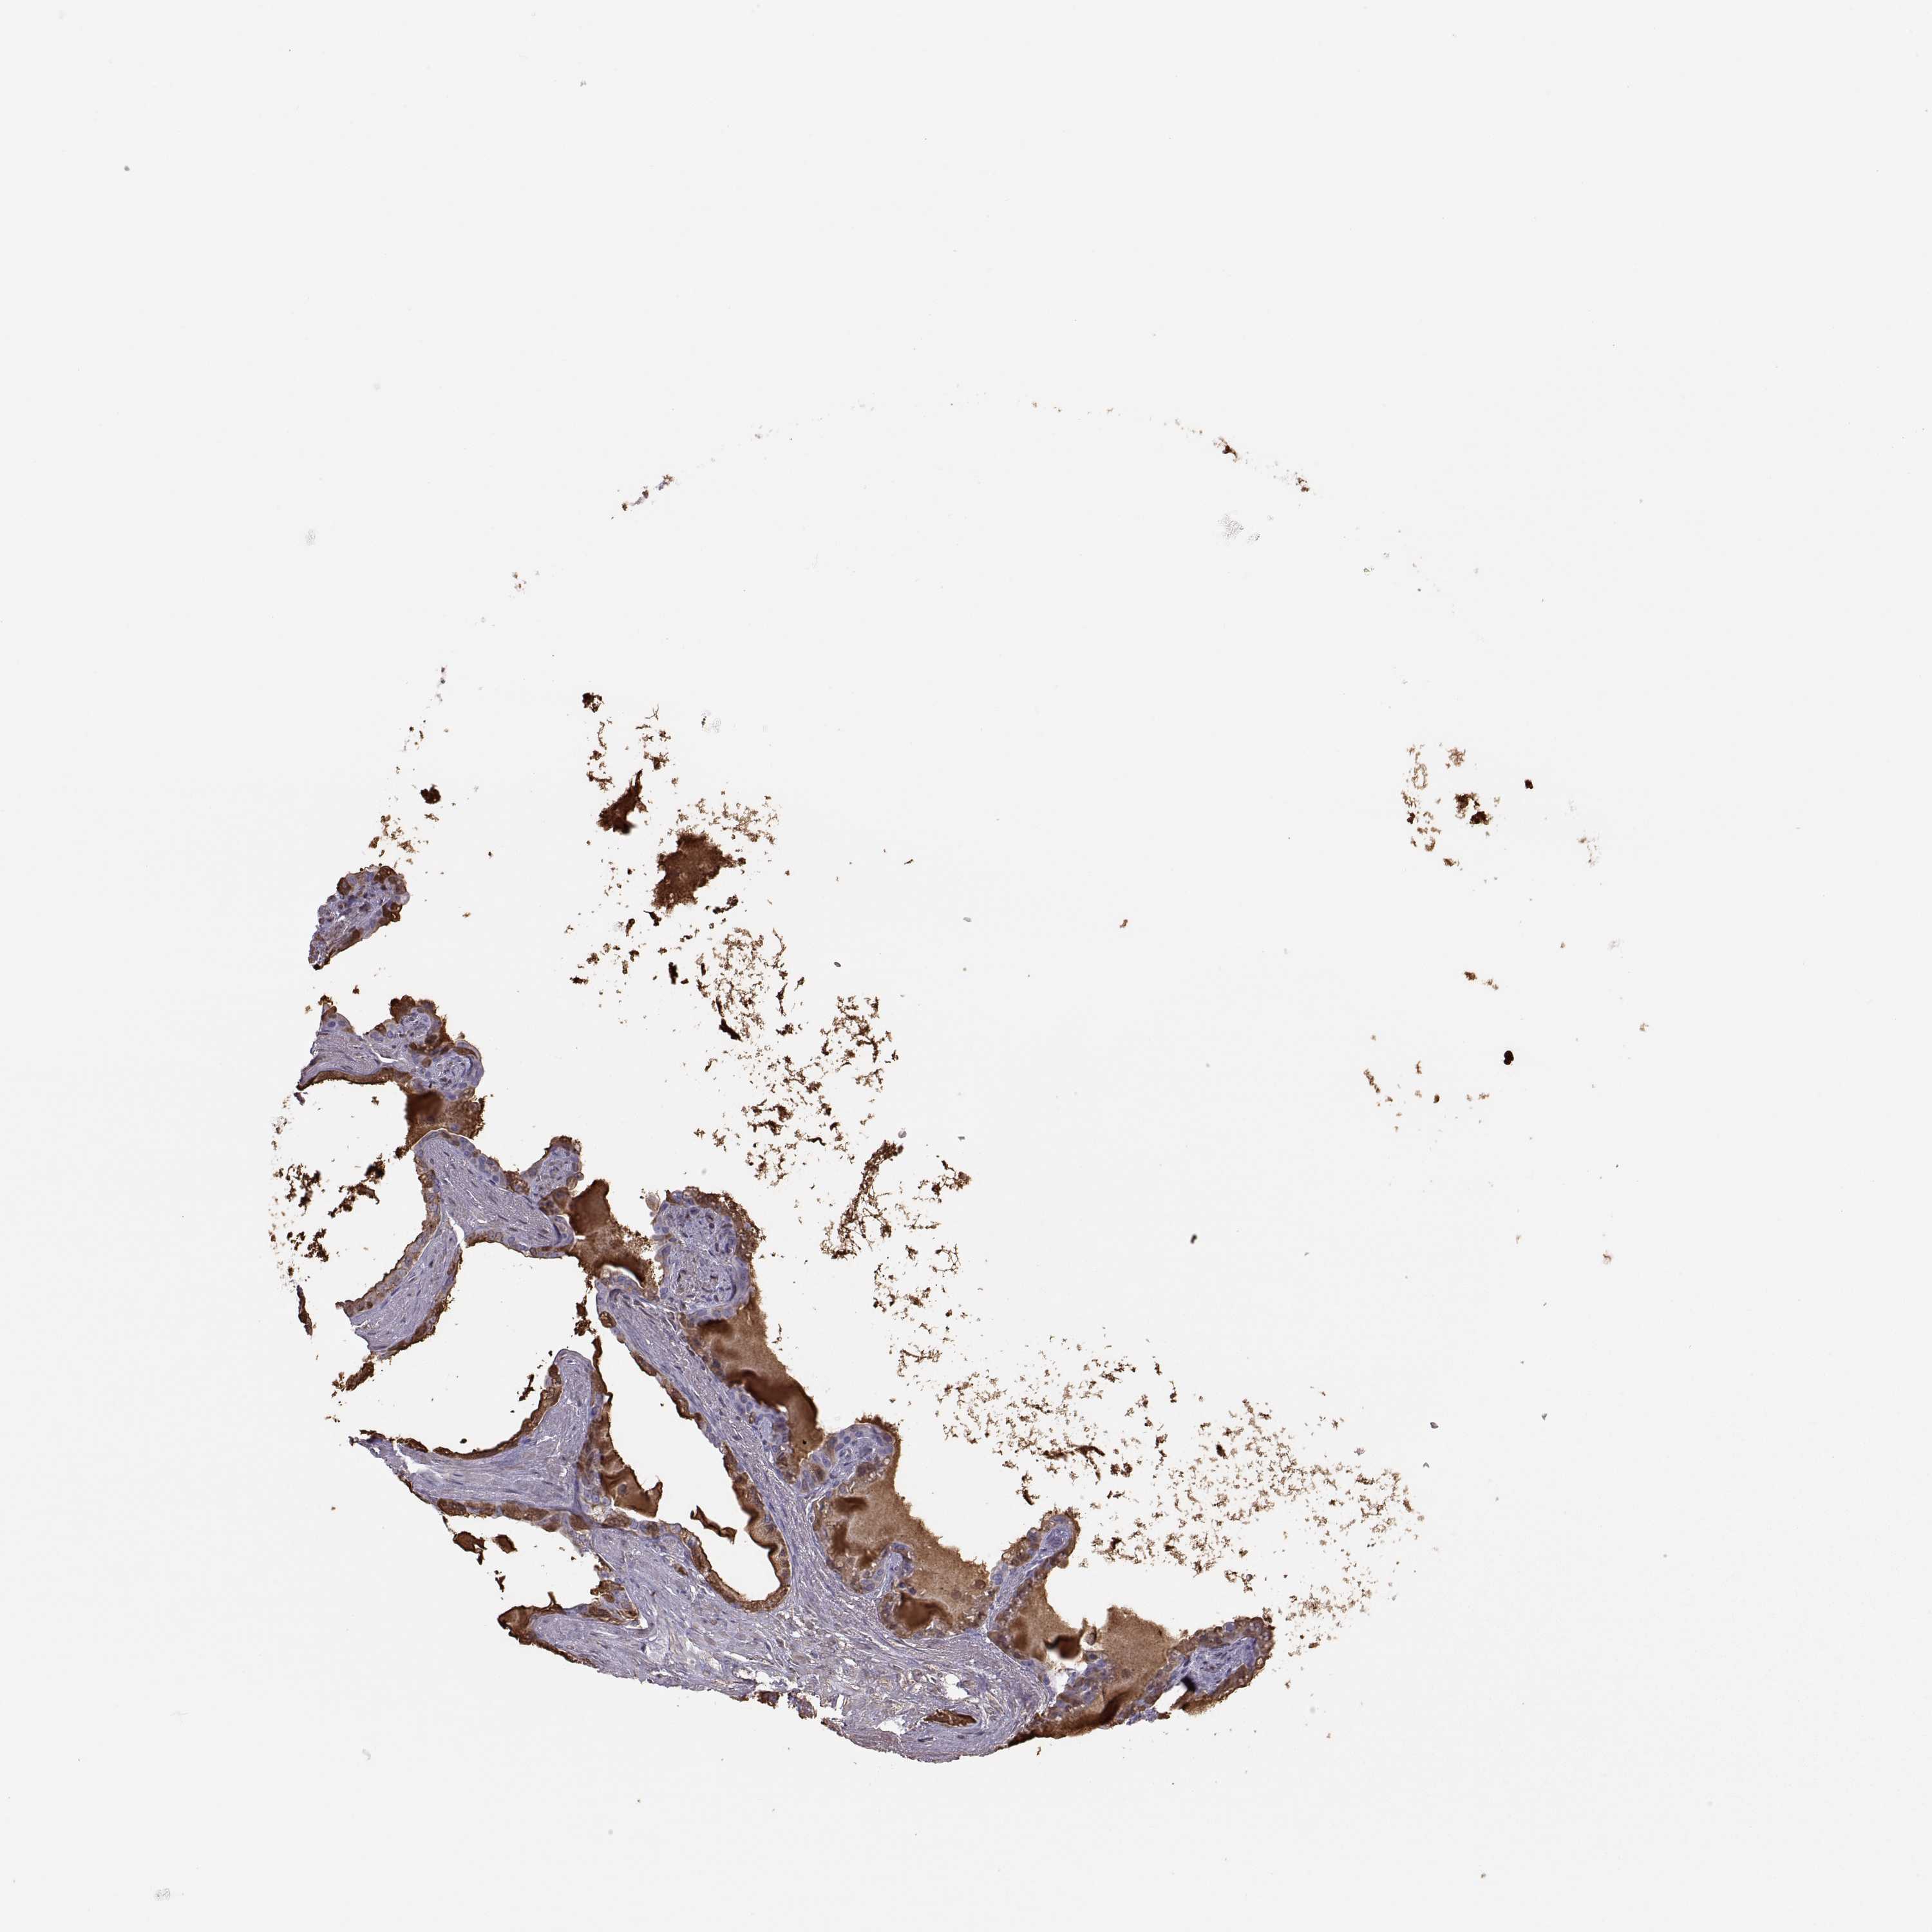

SEMINAL VESICLE - Antibody stainingi

Antibody staining in the annotated cell types in the current human tissue is reported as not detected, low, medium, or high, based on conventional immunohistochemistry profiling in selected tissues. This score is based on the combination of the staining intensity and fraction of stained cells.

Each image is clickable and will lead to virtual microscopy that enables deeper exploration of all samples and also displays staining intensity scores, fraction scores and subcellular localization as well as patient and tissue information for each sample.

Antibody HPA042476Antibody HPA064892

Glandular cells HighHigh